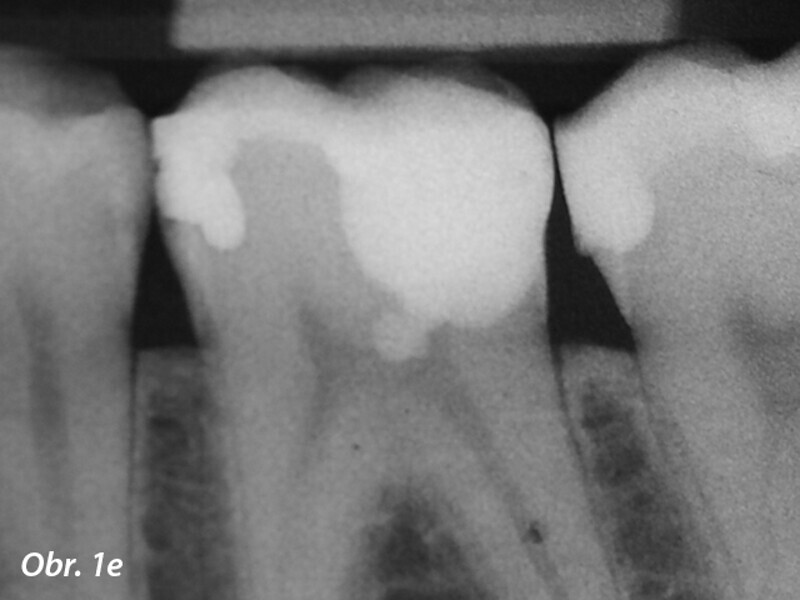

Aplikace MTA s použitím Produit Dentaires (PD) MAP System